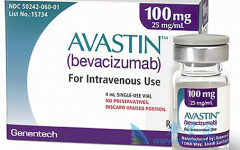

国际辐射肿瘤学,生物学和物理学杂志发表的一篇文章报道了放射治疗肿瘤学组(RTOG)贝伐单抗(阿瓦斯汀)II期临床试验以及顺铂和盆腔放射治疗局部晚期 宫颈癌 的结果。该研究小组报告说,将阿瓦斯汀加入到现有的护理标准中是安全的,并显示出有希望的总 ...

宫颈癌是35岁及以下女性中常见的 妇科癌症 之一。“新英格兰医学杂志”发表的数据显示,阿瓦斯汀(贝伐单抗)相比单独化疗可延长35岁一下晚期宫颈癌患者生存期。在过去的十年中,英国的宫颈癌发病率在英国上升了大约15%,2010年确诊了2,900名妇女。到目 ...

Genentech生物技术公司表示,抗癌药物 阿瓦斯汀 在六个月内治疗脑癌时表现出积极的结果。该公司表示,阿瓦斯汀的一项中期研究显示,有36%的患者接受该药物治疗6个月后无复发性多形性胶质母细胞瘤生长。与此同时,有51%的参与者与化疗联合使用的患者在6 ...

罗氏宣布,随着美国FDA的批准, 阿瓦斯丁 现在将受益于患有晚期非小细胞肺癌(NSCLC)。该批准基于关键的III期临床试验数据(E4599),该数据显示,与单独使用化疗相比,阿瓦斯汀联合铂类化疗(卡铂联合紫杉醇)治疗的患者生存获益良好。罗氏全球医药发 ...